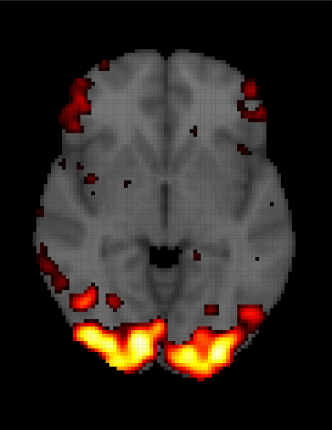

for and , where is the number of voxels in the fMRI array and is the number of observations in each time series. and are the observed (obtained from the scanner) and expected ( obtained from equation 1.2) BOLD response, respectively. Then the parameter will inform about the time series voxels () that match with expected BOLD response . In this type of modeling, a key feature of any fMRI dataset is totally ignored: the spatio-temporal relationships. Thus, in the model 1.3, independent observations inside each voxel (temporal independence) are assumed, as is independence among voxels (spatial independence), both unrealistic suppositions. One of the main consequences of performing this type of analysis is getting incorrect inferences about the parameter and a high rate of false positives, in other words, identifying a brain activation when it really does not exist. A common practice to fix this problem is to use some sort of corrections, like the Bonferroni correction or spatial extent methods (Worsley \BBA Friston (\APACyear1995)), among others. For instance, in figure 1.6 we can see an example of an activation of the visual cortex. In the left panel, the inference is performed without any type of correction and in the right panel, a Bonferroni correction is used. From this example, we might think that this kind of method could help solve the problem of detecting a false activation pattern. However, Eklund \BOthers. (\APACyear2012) and Eklund \BOthers. (\APACyear2016) evaluate the most common software packages for fMRI analysis using real data, and they find that in general, those correction methods do not work very well. Specifically, they use resting-state data and a total of 3 million random task group analyses to compute empirical familywise error rates. For a nominal familywise error rate of 5%, parametric statistical methods are shown to be conservative for voxelwise inference (e.g., using the Bonferroni method) and invalid for clusterwise inference (e.g., using spatial extent methods).

| (a) | (b) |

|---|---|

![]() |